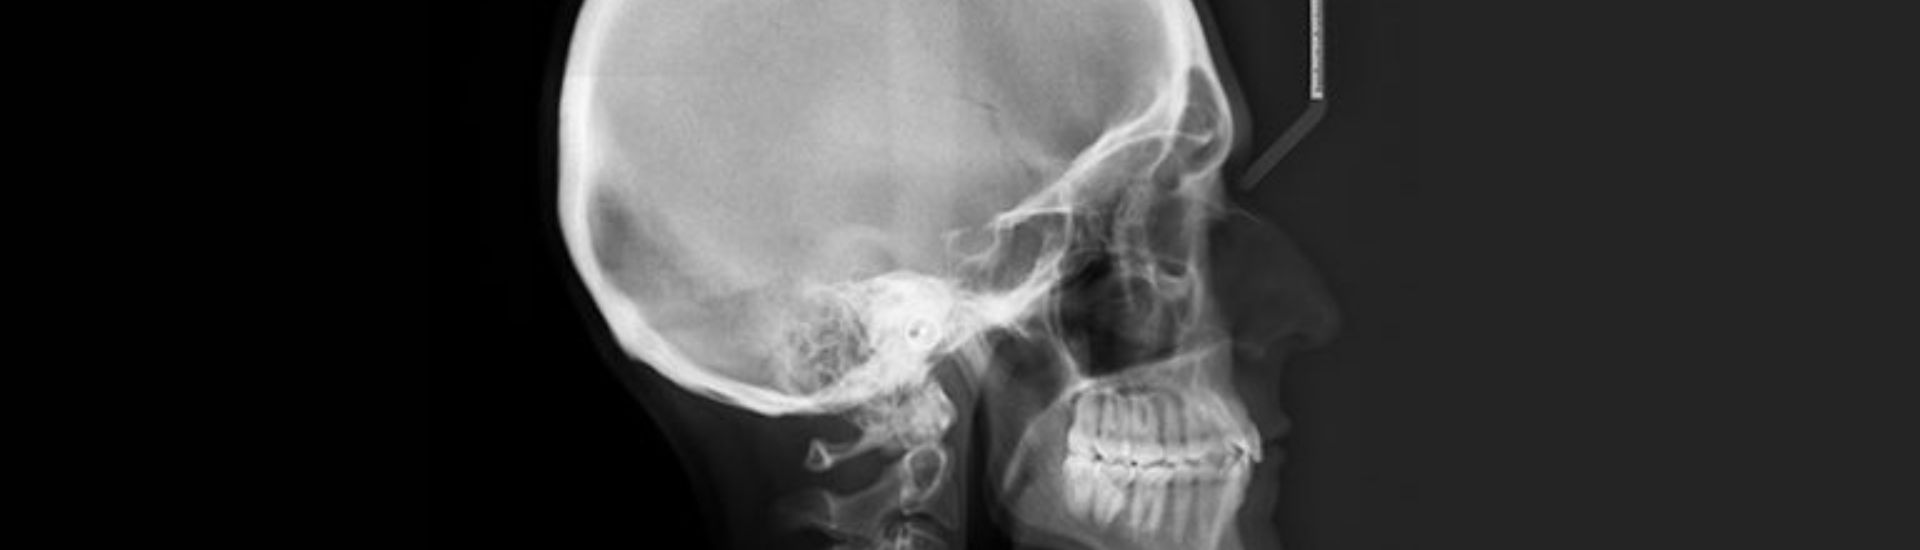

La Teleradiografia Cranio per Cefalometria è un esame radiologico non invasivo, fondamentale per l’analisi dettagliata della struttura cranio-facciale. Questo esame è spesso utilizzato nell’ortodonzia e nella chirurgia maxillo-facciale per valutare le relazioni tra le diverse componenti scheletriche del cranio e i denti. Al Poliambulatorio S-Medical Group di Sora, l’esame viene eseguito con tecnologie di ultima generazione e sotto la supervisione di professionisti esperti, garantendo massima precisione e affidabilità.

La Teleradiografia Cranio per Cefalometria è una metodica diagnostica che sfrutta le immagini radiografiche per ottenere una visione chiara e precisa delle strutture cranio-facciali. Questa tecnica è indispensabile per valutare la crescita e lo sviluppo del cranio e della mascella, fornendo dati essenziali per pianificare trattamenti ortodontici e chirurgici.

L’esame viene eseguito posizionando il paziente in piedi o seduto, con il capo stabilizzato per garantire una corretta acquisizione delle immagini. Durante l’esposizione, l’apparecchio radiologico cattura una visione panoramica del cranio e delle strutture circostanti, permettendo di misurare angoli, distanze e proporzioni che sono fondamentali per una diagnosi accurata.

Le immagini ottenute vengono successivamente elaborate con software avanzati, che aiutano a eseguire un’analisi cefalometrica dettagliata, evidenziando eventuali discrepanze scheletriche e dentali.